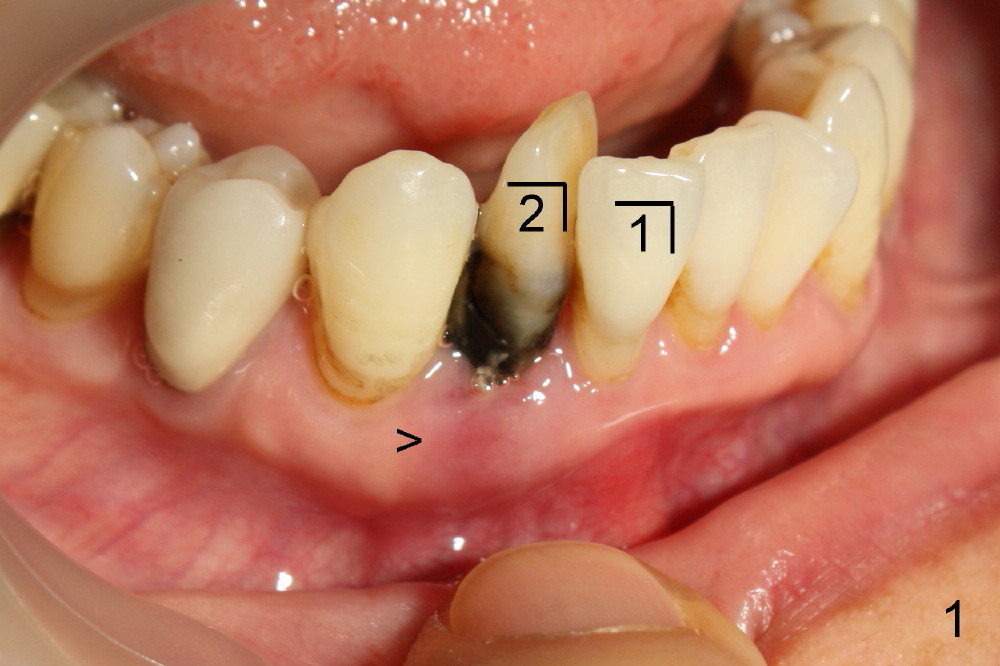

A 60-year-old lady wants to remove 2 mobile lower right incisors (Fig.1,2; with infection at the lateral (>)). Immediate 1-piece implants are placed (Fig.3,4): 3x17 mm at the central, 3.5x17 mm at the lateral. Insertion torque is > 60 Ncm for the implants. No bone graft is placed. After prep (Fig.5), two separate provisionals are fabricated (Fig.6). The one at the lateral incisor looks bulky at the cervix, because of the oversized implant for the site (over-engineering). Use of smaller implant (3.0 (instead of 3.5), 2.5 (instead of 3.0) or 2.0 mm) may solve the problem. Seven days postop, the infection resolves (Fig.7 >) with normal-looking papilla (*).